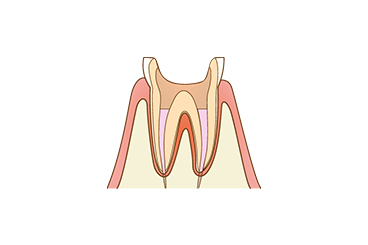

【5】根管を充填

清掃した根管内に薬剤を詰めて、完全にすき間をふさぐことで感染を防ぎます。